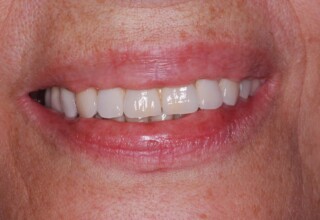

Ολική Στοματική Αποκατάσταση σε Εμφυτεύματα με διαφορετική προσέγγιση στην Άνω και Κάτω Γνάθο

Κάτω γνάθος: εξαγωγές, άμεση τοποθέτηση εμφυτευμάτων και άμεση φόρτιση(την ίδια ημέρα) με προσωρινή γέφυρα

Άνω γνάθος: σταδιακές εξαγωγές, σταδιακή τοποθέτηση εμφυτευμάτων και σταδιακή ενσωμάτωση τους στην προσωρινή γέφυρα ώστε η ασθενής να μην μείνει ούτε μια ημέρα χωρίς αποκατάσταση. Στόχος η συνεχής λειτουργική και αισθητική αποκατάσταση της ασθενούς χωρίς άμεση φόρτιση των εμφυτευμάτων λόγω ανατομικών ιδιαιτεροτήτων.

Χρησιμοποιήθηκαν παλαιές χαμογελαστές φωτογραφίες της ασθενούς γιατί είχε χαθεί τελείως το φυσικό σχήμα των δοντιών εξαιτίας των πολλαπλών προσθετικών προσπαθειών που είχαν γίνει στο παρελθόν. Μεταφέρθηκε στην προσωρινή γέφυρα η σχέση των φυσικών δοντιών μεταξύ τους άλλα και με τα χείλη. Δοκιμάστηκε η φώνηση και η μάσηση με δυο διαφορετικές προσωρινές άνω γέφυρες και εκτιμήθηκε η αισθητική απόδοση τους. Αφού επιτεύχθηκαν σε βαθμό ικανοποιητικό η φώνηση και η αισθητική εμφάνιση της οδοντοφυΐας, η προσωρινή αποκατάσταση χρησιμοποιήθηκε ως οδηγός για την τελική.

Αρχικό

Ενδιάμεσο

Τελικό